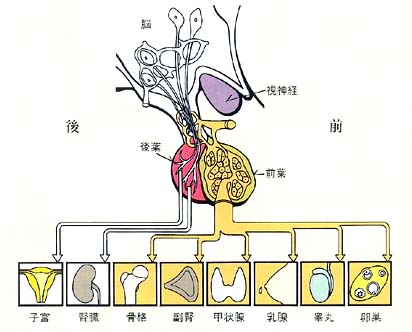

一ロでいうと、全身のホルモン(内分泌)の中枢です。前葉、後葉ともに多くの支配ホルモンを分泌していますが、そのうち特に重要なものを挙げてみます。

前葉のホルモン

(1)成長ホルモン

小児期から思春期にかけて、手足や内臓の成長を促します。成人になると大きな意義はなくなりますが、最近、性欲・意欲・体脂肪に関連するといわれています。

(2)プロラクチン

分娩後に乳汁を分泌させる働きをします。また、このホルモンが多量に分泌されている間は月経は止まっています。男性や産褥期以外の女性では大きな意義はありません。

(3)甲状腺刺激ホルモン

(4)副腎皮質刺激ホルモン

甲状腺や副腎に命令して、おのおののホルモンを分泌させる働きをします。男女とも生涯必要です。

(5)性腺刺激ホルモン

これには2種類あり、それぞれ卵胞刺激ホルモン、黄体化ホルモンといいます。男性では睾丸を女性では卵巣を支配し、おのおの性ホルモンの分泌を促します。さらに、精子や卵子の正常な発育にも重要なホルモンです。

後葉のホルモン

(1)抗利尿ホルモン

腎臓に働きかけて尿量を少なくする働きをします。男女とも生涯必要です。

(2)子宮収縮ホルモン

分娩時に子宮を収縮させます。これ以外には通常男女とも大きな意義はないようです。